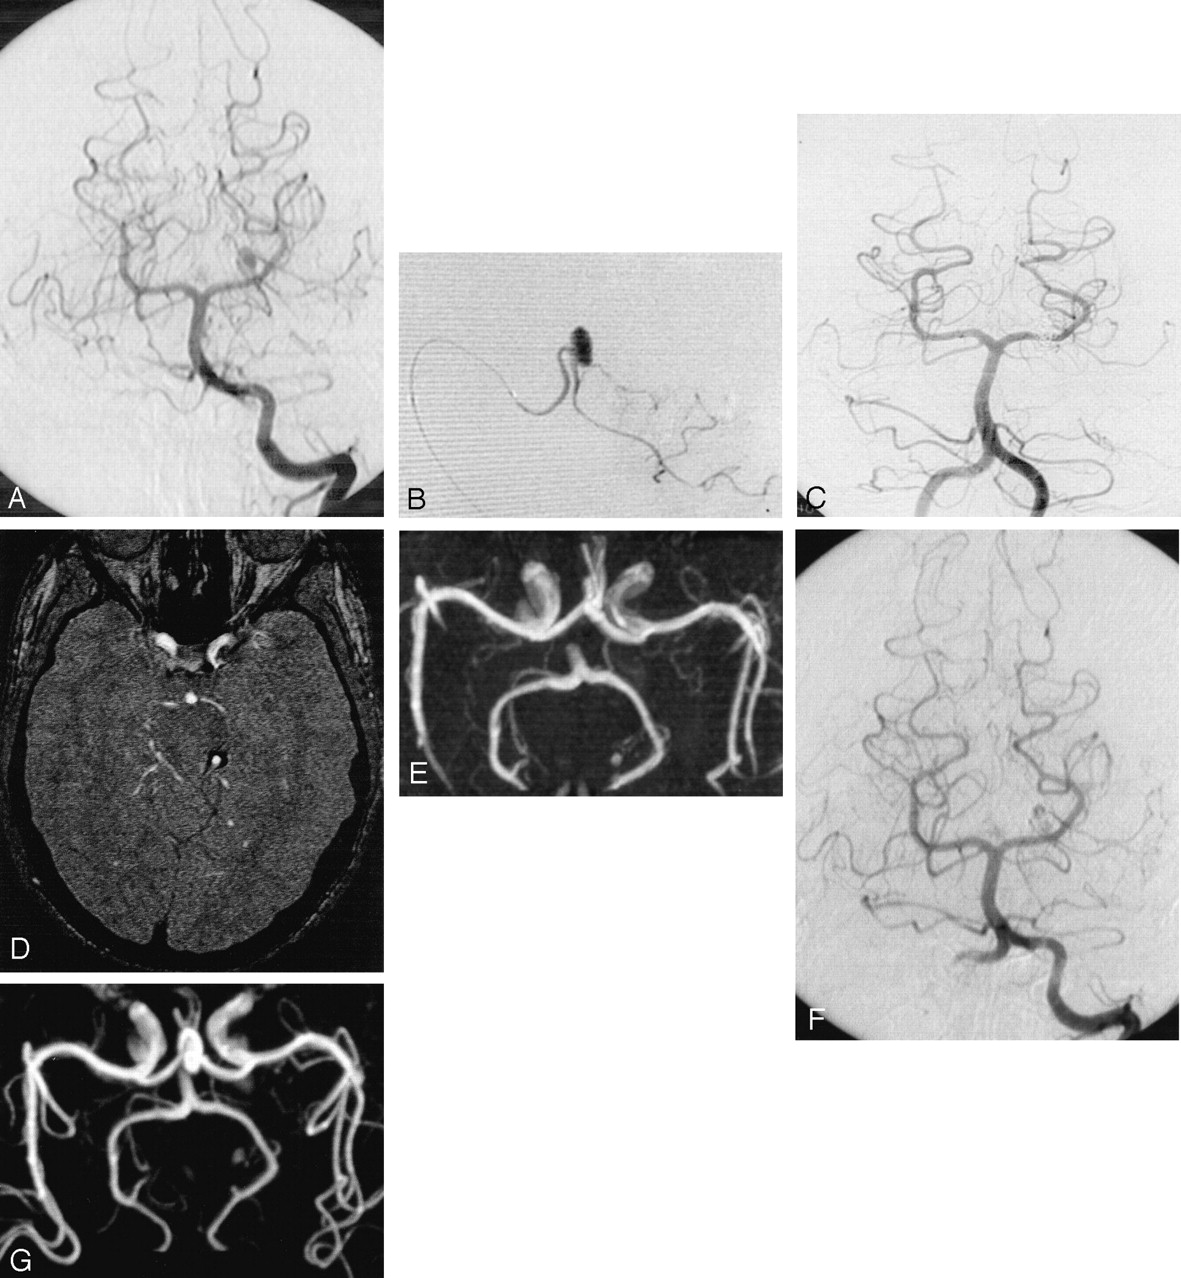

Selective embolization (Fig 1) was performed in five patients who each had a small aneurysm with a small neck. Complete occlusion was achieved in two patients, a neck remnant was present in each of two, and residual flow was observed in one. Parent artery occlusion (Fig 2) performed in large peripheral cerebellar artery aneurysms (two patients) or in a small aneurysm with a wide neck (one patient) led to complete aneurysmal thrombosis.

Incidental aneurysm revealed by MR image of a 16-year-old male patient who complained of headaches.

A, Cerebral angiogram of the right vertebral artery shows large dysplastic aneurysm located 2 cm distal to the origin of the posterior inferior cerebellar artery.

B, Contrast-enhanced axial view T1-weighted image shows a partially enhanced mass close to the right part of the medulla.

C, Nonsubstracted control angiogram obtained immediately after occlusion by coils of the posterior inferior cerebellar artery at its origin shows complete occlusion of both the aneurysm and the parent vessel.

D, Axial view T1-weighted image obtained at 6 months shows complete disappearance of mass effect.

E, Follow-up conventional angiogram obtained at 12 months reveals no aneurysm recurrence.

F, Follow-up MR angiogram obtained at 36 months reveals no aneurysm recurrence.

Follow-up conventional angiograms and MR angiograms were obtained for all patients. Mean duration of follow-up was 18.5 months. MR imaging and MR angiography performed at 6 months after treatment were in accordance with the results of the conventional angiography performed at 12 months. All five aneurysms that were completely occluded after endovascular treatment remained unchanged. Control angiography and control MR imaging performed at 1 year for patients with neck remnants shown by postprocedural angiography (two patients) showed further thrombosis with complete occlusion of the malformation (patients 2 and 6). In one patient with a superior cerebellar artery aneurysm and residual flow, the degree of occlusion remained unchanged 36 months after treatment (Fig 1). This patient’s follow-up included MR angiography, and no further treatment was planned. All patients remained clinically unchanged during the follow-up period; one patient (patient 7), therefore, still had VIIth cranial nerve palsy.